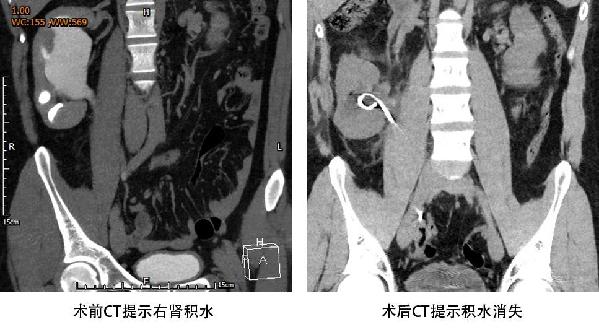

术后第一天,段晓伟就能下床活动,术后第二天复查肾积水消失,术后第三天患者就康复出院了。出院时,段晓伟的妈妈拉着马鑫的手说:“谢谢您救了我儿子,我一辈子都会感激您!”

患者术前术后CT对比右肾积水情况。(301医院提供)